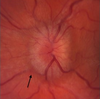

C shape halo with temporal disc margin sparing No elevation No vessel obscuration = Grade 1

178

Circumferential halo Elevation of nasal border No vessel obscuration = Grade 2

179

Circumferential halo Elevation of all borders Obscuration of one vessel leaving the disc = Grade 3

180

Circumferential halo Complete elevation including the cup Obscuration of a major vessel on the disc = Grade 4

181

Circumferential halo Complete elevation including the cup Obscuration of all vessel on the disc and leaving the disc = Grade 5

182

Papilloedema Optic nerve sheath diameter less than 5mm is normal in adults Occular Point of care ultrasound